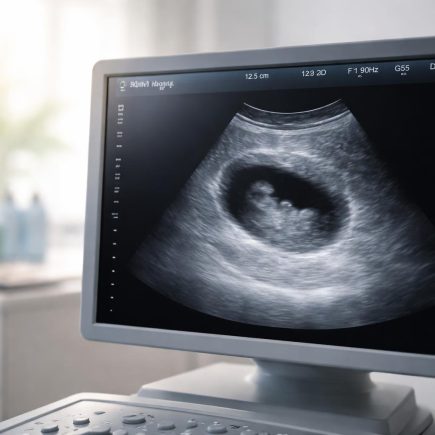

Écho 9SA : Que Voit-on à l’Échographie ?

Vous arrivez à votre examen et vous vous demandez ce qui va apparaître sur l’écran ? Est-ce que le bébé ressemble déjà à un petit humain ? Est-ce qu’on peut entendre son cœur battre à ce stade ? L’échographie à 9 SA (semaines d’aménorrhée) est un moment charnière où l’embryon commence sa mutation pour devenir …

Écho 6SA : Que Voit-on sur l’Échographie ?

Vous attendez votre première échographie de datation avec un mélange d’impatience et d’appréhension ? Vous vous demandez ce qu’il est réellement possible de voir sur l’écran à ce stade précis ? Est-ce normal de ne pas encore distinguer de forme humaine ou d’entendre le cœur ? Cet article vous explique en détail ce que votre …